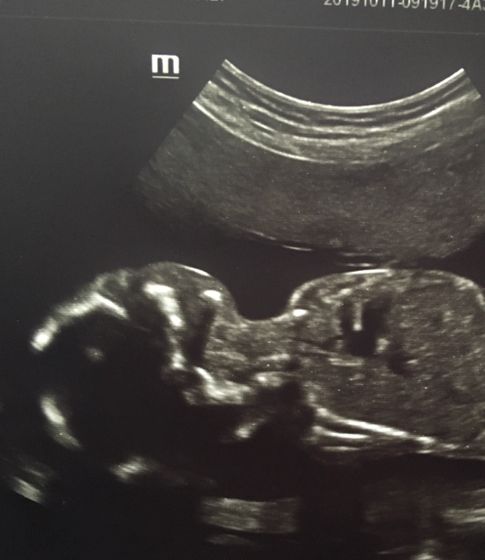

Вот и половина беременности позади, а казалось что только недавно увидела на тесте надпись: беременна, и вроде только недавно был первый скрининг, а уже второй прошли ? какие сладкие щёчки у малыша нашего.

Наш мальчик, питается во всю, особенно после того как съем сладкое)))(первые толчки были в 16 недель) мне кажется в первую беременность ?? время шло медленнее а сейчас так всё быстро ?